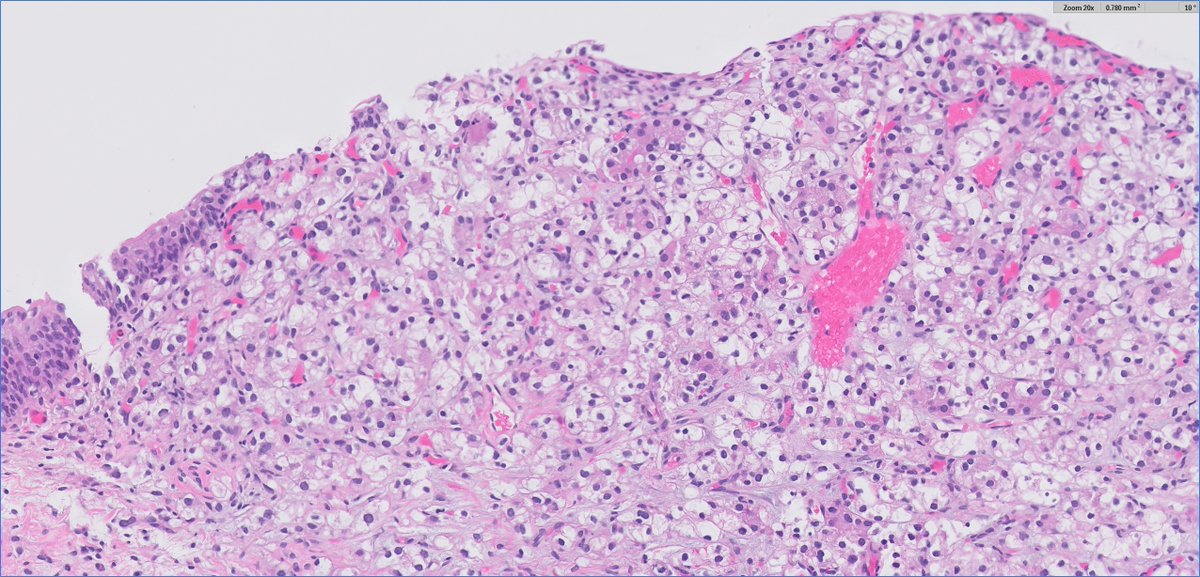

CC357. Long-standing hemopericardium. We talk a lot about molecular biology and very little about cell biology. One of those peculiar cytologic findings with no histological counterpart, so far Barry McGinn Kalyani Bambal Lorand Kis Mark Ong